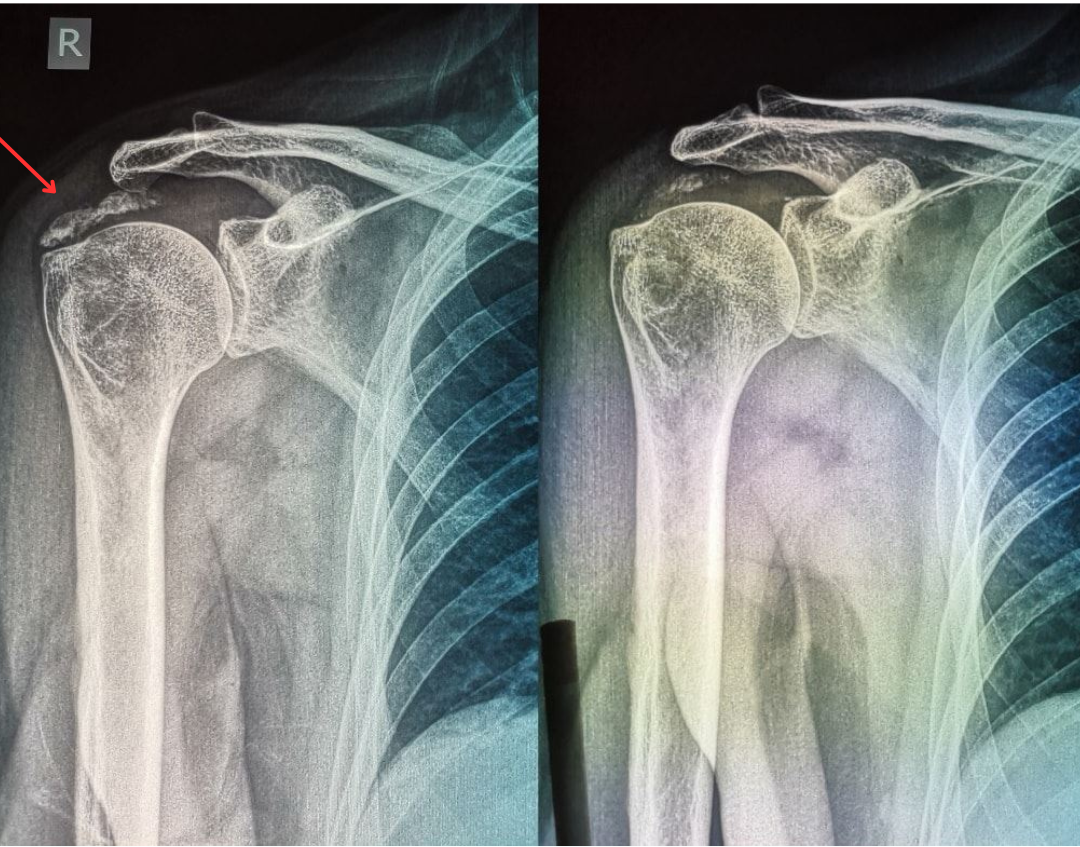

- Ασβέστωση